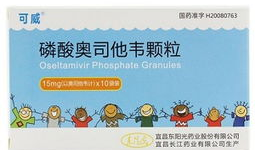

奥司他韦的作用与功效,流感病毒克星,高效抗病毒治疗新选择

你有没有听说过奥司他韦这个名字?这可是个在感冒发烧时能派上大用场的宝贝呢!今天,就让我来给你详细介绍一下奥司他韦的作用与功效,让...